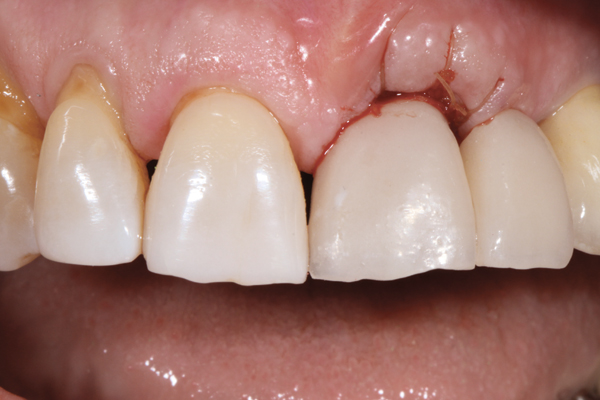

In order to maximize the height of the peri-implant papilla, significant efforts must be made to maximize the blood supply and to preserve the bone on the adjacent roots and between the implant.12 Pressure and blanching of the peri-implant tissues compromises the blood supply of this fragile complex and (eventually) leads to reduction in the height of the papilla (Figure 3). At a given site in a given individual, there is a natural biologic width that the body will strive to maintain between any bone and any non-integrated material. Thus, if a non-integrating abutment is placed within close proximity to the bone on the adjacent natural tooth (Figure 4), inevitably the bone will be remodeled to a more apical position to re-establish the biologic width. This distance obviously varies, but generally 1 mm to 1.5 mm is needed.13

Fig 3. Placement of abutments that create blanching of the peri-implant soft tissue will result in unpredictable remodeling of the tissue to a more apical position, which may create an esthetically displeasing result. This is best managed in the esthetic zone by shaping the soft tissue in the provisional stage rather than with the definitive abutment.

Figure 3